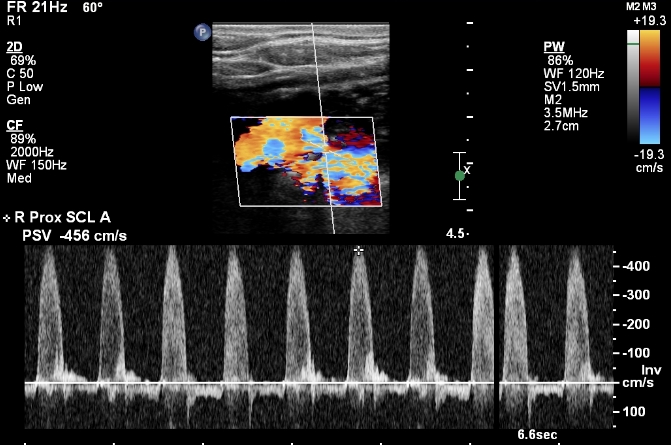

First, check the blood pressure in both arms. If it is equal, that points against significant narrowing. Next, you will need to images the subclavian artery. An ultrasound should be a first step. On ultrasound, elevated flow velocities and turbulent flow are the markers of significant subclavian artery stenosis:

The next step is to use imaging. Imaging will make the diagnosis of the narrowing in the subclavian artery. Obviously, CT and MR are the best types of imaging for this. Then, imaging should identify the reverse flow in the vertebral artery. Duplex ultrasonography is the best type of imaging for identifying flow direction. Here is an example: